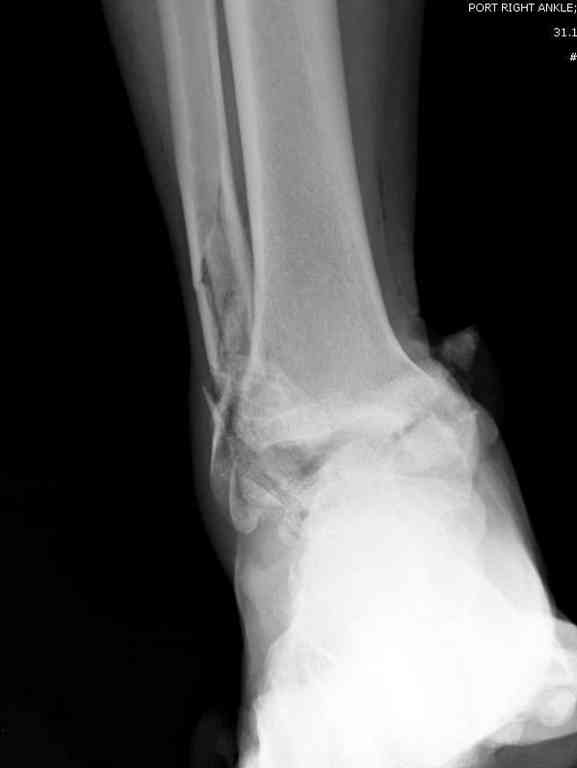

Второй случай прооперирован вчера.

10 дней назад поступил с открытым повреждением медиальной лодыжки и переломо вывихом таранной кости. Ургентно сделана репозиция с наложением наружного фиксатора + Irrigation&Debridment.

Во время репозиции выявили повреждение заднего сухожилия м. тибиалис и задней большеберцовой артерии. Медиальную рану удалось закрыть частично и установлен вакуум.

Дважды провели Irrigation&Debridment с заменой вакуума.

Вчера провели фиксацию.

Из-за многооскольчатости дистальной части малоберцовой, где невозможно было провести фиксацию шурупами, перелом зафиксирован подпирающей пластиной, которая должна служить дополнением отсутствующей дистальной части малоберцовой (lateral cortex substitute).

Для стабильности два шурупа на синдесмоз.

Медиальную рану с приближенными краями продолжаем вакуумировать (KCI). Наружный фиксатор оставлен на пару недель, надеюсь, небольшая рана будет гранулировать и закроется без кожной пластики. Фиксация медиальной ложыжки не планируется.